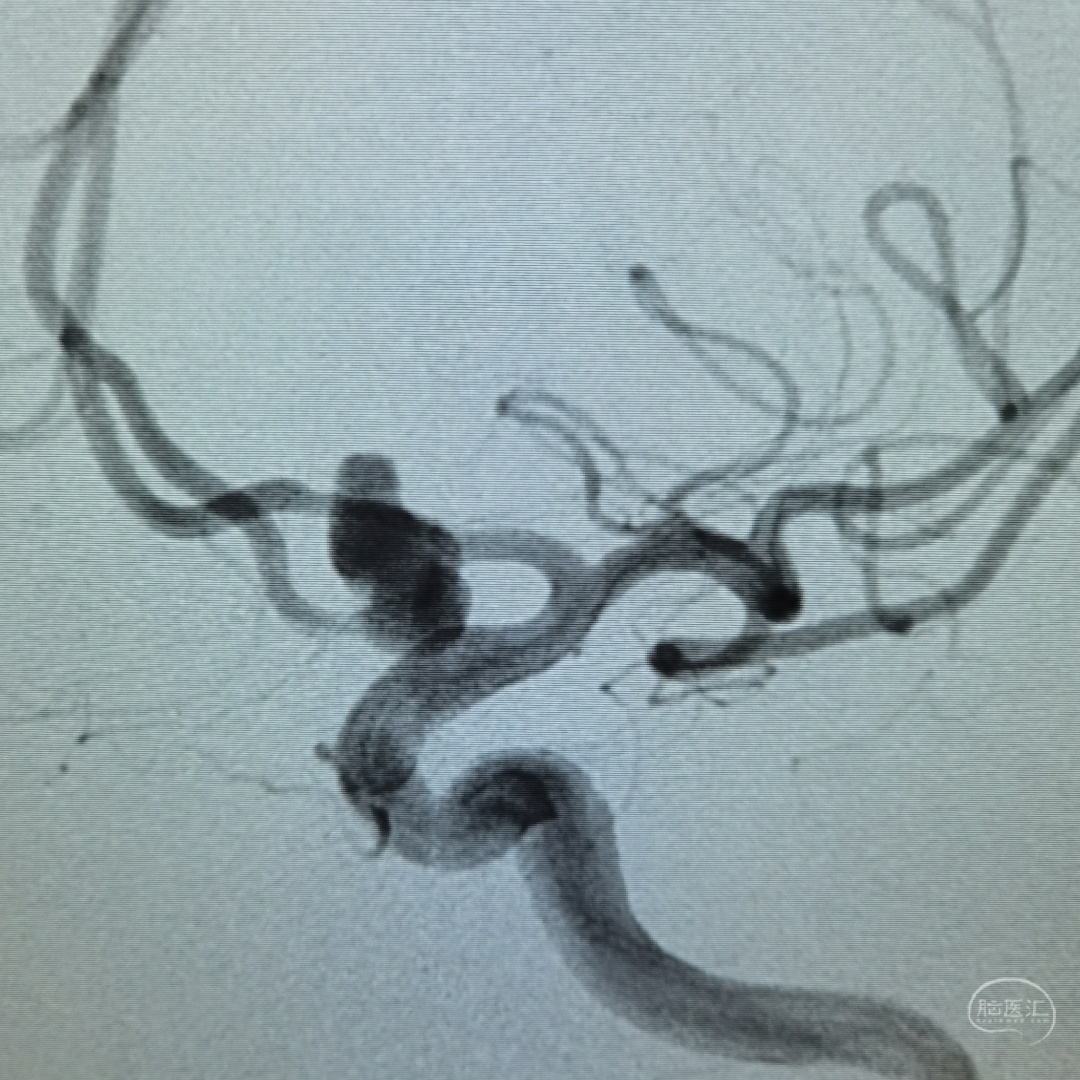

左侧颈内动脉三维旋转造影可见动脉瘤位于前交通部位,累及双侧A2,形态呈长条分叶,顶端可见小子瘤。并可看到双侧a2近端血管痉挛表现

三维重建可见动脉瘤呈葫芦状,动脉瘤瘤颈累及双侧A2,没有满意的工作角度能充分展示动脉瘤瘤颈以及和双侧A2和A1的关系。

工作角度造影可以看到动脉瘤瘤体展示比较清楚,左侧A1全程清晰可见,隐约可以看到双侧A2的开口